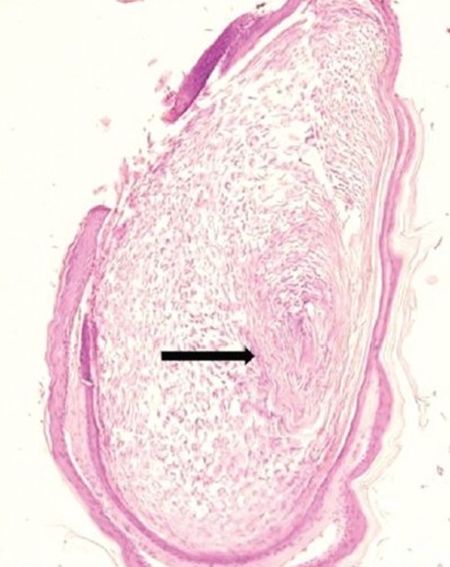

皮损于局部麻醉下切除,标本送病理检查。大体组织为囊状结构,含有软而臭的干酪样物质。镜下见囊壁有复层鳞状上皮和颗粒状细胞层,并含角质物,无附件结构(图2和图3)。

图2. 组织病理:含角质物的囊肿,呈层状排列(黑色箭头),囊壁为复层鳞状上皮(HE染色,×100)